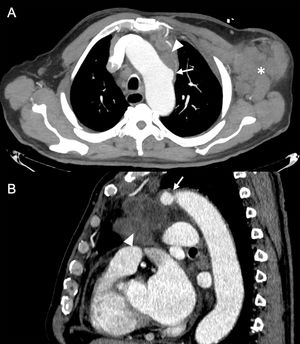

76-year-old man with stage IV urothelial carcinoma in progression and currently undergoing chemotherapy who was admitted for hypoxaemic respiratory failure due to respiratory infection. During admission, he suffered progressive worsening with renal failure and continuous elevation of acute phase reactants. Coronal reconstruction of contrast-enhanced chest CT in arterial phase showing a pericardial effusion (asterisk) with enhancement of the pericardial layers (dashed arrow), as well as a new saccular dilation in the aortic arch related to mycotic pseudoaneurysm (arrow) and a peri-pseudoaneurysmal inflammatory collection (arrowhead). Due to the patient's clinical status and his progressive underlying disease, a conservative approach was taken and the patient’s deterioration led to his death.

A 75-year-old man with long-standing weight loss came in with a left axillary mass. Outpatient ultrasound showed a large clump of lymphadenopathy, so a contrast-enhanced chest CT was performed. Axial maximum intensity projection (A) and sagittal (B) reconstructions confirmed the abnormal left axillary clump of lymphadenopathy (asterisk) and a mediastinal tumour mass (arrowhead) in contact with the aortic arch, with focal saccular dilation of the aorta showing some degree of parietal irregularity, suggestive of pseudoaneurysm (arrow). Histological analysis confirmed that the areas of lymphadenopathy were metastases of squamous cell carcinoma, with pulmonary origin being suspected. The decision was made to start oncological treatment with imaging to monitor response and adopt a conservative approach with the pseudoaneurysm due to the complexity of the intervention because of its location and the underlying invasive lesion.